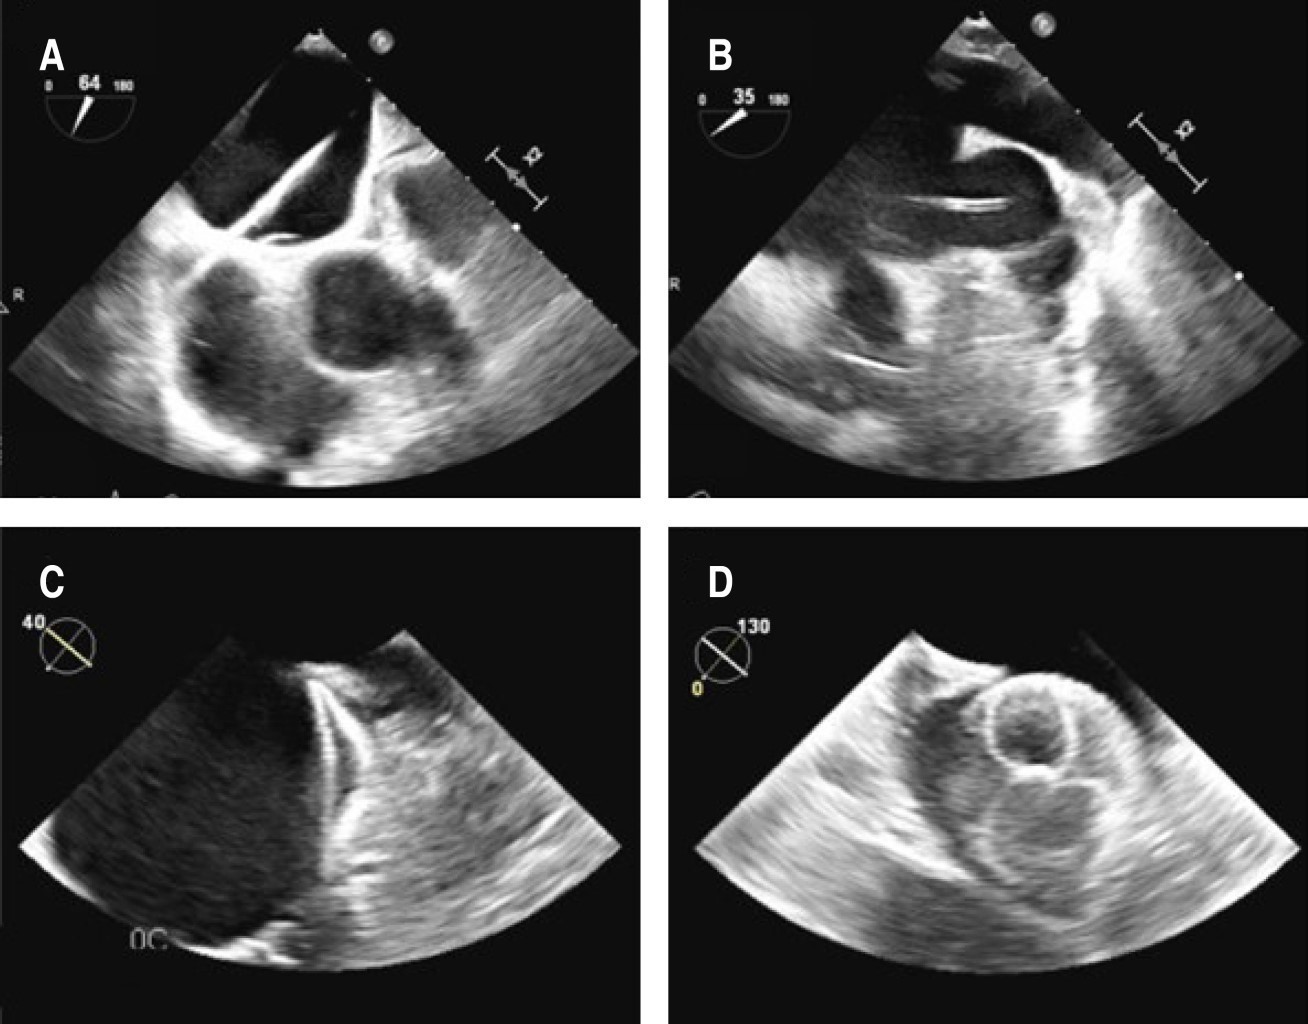

Figura 1

Introducción: al momento de elegir el tratamiento de la fibrilación auricular, es necesario entender al paciente más allá de las puntuaciones de riesgo, comprender la necesidad de llevar a ritmo sinusal o a metas de tratamiento y la rapidez que debe emplearse dado el riesgo que confieran sus enfermedades crónicas y los retos que plantean estas enfermedades a las estrategias convencionales. Presentación de caso: masculino de 69 años, con antecedente de colitis ulcerativa crónica inespecífica (CUCI), intervenido con colectomía subtotal, desde entonces con rectorragia abundante, intermitente. En valoración preoperatoria de hernia paraestomal se descubre FA. Con aumento de rectorragia tras inicio de anticoagulación, abundante en cantidad, llegando a requerir hospitalización. Por el estado de hipercoagulabilidad e inmuno-tromboinflamación asociada a CUCI, se consideró prioritario revertir a ritmo sinusal. Se intenta sin éxito cardioversión farmacológica con amiodarona. Fue considerado candidato para realizar ablación con crioterapia tras cardioversión eléctrica fallida, además de cierre de orejuela izquierda por considerarse no candidato a anticoagulación a largo plazo. Se realiza crioablación de las cuatro venas pulmonares sin lograr retorno a ritmo sinusal, por lo que se amplía ablación hacia pared posterior y orejuela izquierda, con lo que se logra yugular la arritmia exitosamente. Por último, se coloca dispositivo de cierre de orejuela izquierdo. Tras tres meses de tratamiento médico óptimo tras cirugía se retira anticoagulación, a más de un año del procedimiento el paciente se encuentra libre de eventos trombóticos y hemorrágicos. Conclusiones: este caso demuestra la importancia de individualizar el abordaje en la fibrilación auricular. Además, la importancia de la ablación extendida en la fibrilación auricular sin origen en las venas pulmonares, así como el cierre del apéndice auricular como estrategia de tratamiento en pacientes en escenarios complejos no candidatos a anticoagulación.